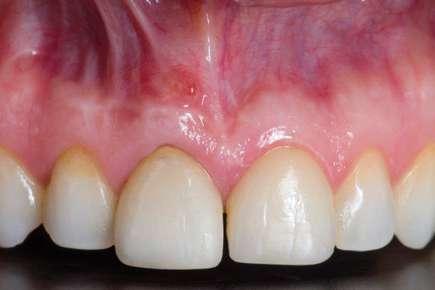

na paciente de 35 años (Figura 1) fue remitida a la Clínica de Odontología Reconstructiva de la Universidad de Zúrich debido a una infección crónica en el diente 11 y con expectativas estéticas muy altas. El diente 11 había sufrido un trauma hace 10 años y había sido tratado con multiple endodoncias sin éxito. El diente presentaba un absceso bucal (Figura 2), una bolsa periodontal aislado de 9 mm, y una ausencia de la tabla vestibular ósea (Figura 3). El diagnóstico se estableció como una fractura radicular vertical, lo que resultó en un pronóstico pobre. El plan de tratamiento consistió en una extracción combinada con preservación alveolar, colocación de implante diferido con injerto de tejido conectivo, una corona cerámica implantosoportada en 11 y una nueva carilla de cerámica para el diente 21.

El diente 11 fue extraído (Figura 4), seguido por la preservación alveolar. Se realizó un injerto pediculado de espesor parcial rotado del paladar (Figura 5), junto con una membrana de colágeno reabsorbible, un xeno-injerto bovino y cianoacrilato sellando al alveolo (Figura 6). La provisionalización consistió en un puente adhesivo de resina con dos alas de metal. El alveolo se dejó cicatrizar durante 6 meses, después de los cuales se tomó una impresión digital así como un escáner CBCT (Figura 7). Se llevó

a cabo una planificación digital para una cirugía guiada de implante en una posición protéticamente ideal (Figura 8). El implante 11 se colocó completamente guiado a través de una férula (Figura 9). Las dimensiones del reborde alveolar eran ideales para la colocación del implante en una posición atornillada (Figura 10), al igual que la calidad del hueso cicatrizado. Un injerto de tejido conectivo subepitelial fue estabilizado ocluso-bucalmente al implante (Figura 11) y el puente adhesivo fue recementado (Figura 12). Después de 3 meses de cicatrización, se realizó una restauración provisional y se acondicionó adecuadamente para dar forma al perfil de emergencia, imitando el del diente adyacente (Figura 13). Después de una fase provisional, se tomó una impresión analógica individualizada para el implante 11 y el diente 21 (Figura 14). El laboratorio fabricó una corona implantosoportada de zirconio con cerámica estratificada para el 11 y una carilla laminada feldespática para el diente 21 (Figura 15). Ambas restauraciones fueron colocadas en la paciente y mantenidas. La paciente quedó muy satisfecha con el resultado estético de las restauraciones (Figuras 16, 17). Después de 2 años, el implante permanece saludable con el hueso marginal estable (Figura 18) y una buena calidad y cantidad de tejido blando.

Conclusiones

Una correcta planificación digital fue clave para definir los objetivos del tratamiento y el manejo detallado de un caso complejo en una paciente con alta demanda estética. Realizar la preservación alveolar para mejorar las dimensiones volumétricas antes de la colocación del implante facilitó una implantación

guiada sin necesidad adicional de aumento de cresta. La planificación digital con cirugía guiada permitió la implantación en una posición atornillada ideal. La fase de provisionalización consiguió dotar al perfil de emergencia de una apariencia estética y natural. Las dos restauraciones cerámicas resultaron simétricas y muy estéticas para una paciente satisfecha. 